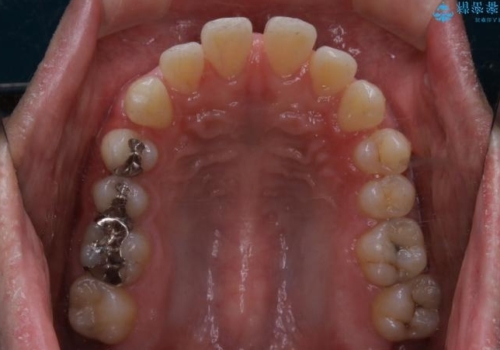

- 全体的に歯と歯の間に隙間があるのが気になるとのことで来院されました。インビザラインでの矯正治療をご希望されました。

隙間については、前歯と奥歯に多数あります。また、上下前歯は、外側に少し倒れているため隙間を閉じつつ、前歯を内側に引っ込めて並べることになりました。

インビザライン・ライトにて矯正治療を行うことになりました。